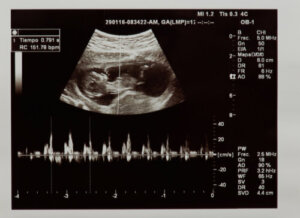

Per frequenza cardiaca intendiamo il numero di volte in cui il cuore si contrae in un minuto. La frequenza cardiaca fetale è identificabile nelle prime settimane di gestazione mediante ecografia o un monitor noto come Doppler fetale.

In un primo momento si valuta se il battito cardiaco è effettivamente presente, verificando così la vitalità fetale. Inoltre, viene valutato quante volte il cuore batte in un minuto. I valori considerati normali in fase fetale sono compresi tra 120 e 160 battiti al minuto.

La valutazione dell’anatomia e della fisiologia del cuore del bambino può essere eseguita dall’utero. Questo grazie agli ultrasuoni eseguiti nei check-up prenatali che ci consentono di valutare, tra gli altri parametri, la salute del cuore e il battito cardiaco fetale.

Certamente, durante il secondo trimestre , è indicata l’ecografia morfologica, dove vengono studiati in dettaglio gli organi del bambino. Qui, le strutture cardiache fetali, come le camere del cuore, le valvole e i vasi sanguigni, sono osservate da vicino.

Con esso si valuta anche il funzionamento del cuore e se c’è qualche problema nel suo meccanismo o conduzione. Inoltre, l’ecografia morfologica diagnostica l’esistenza di malattie cardiache congenite che possono causare problemi dopo la nascita del bambino.